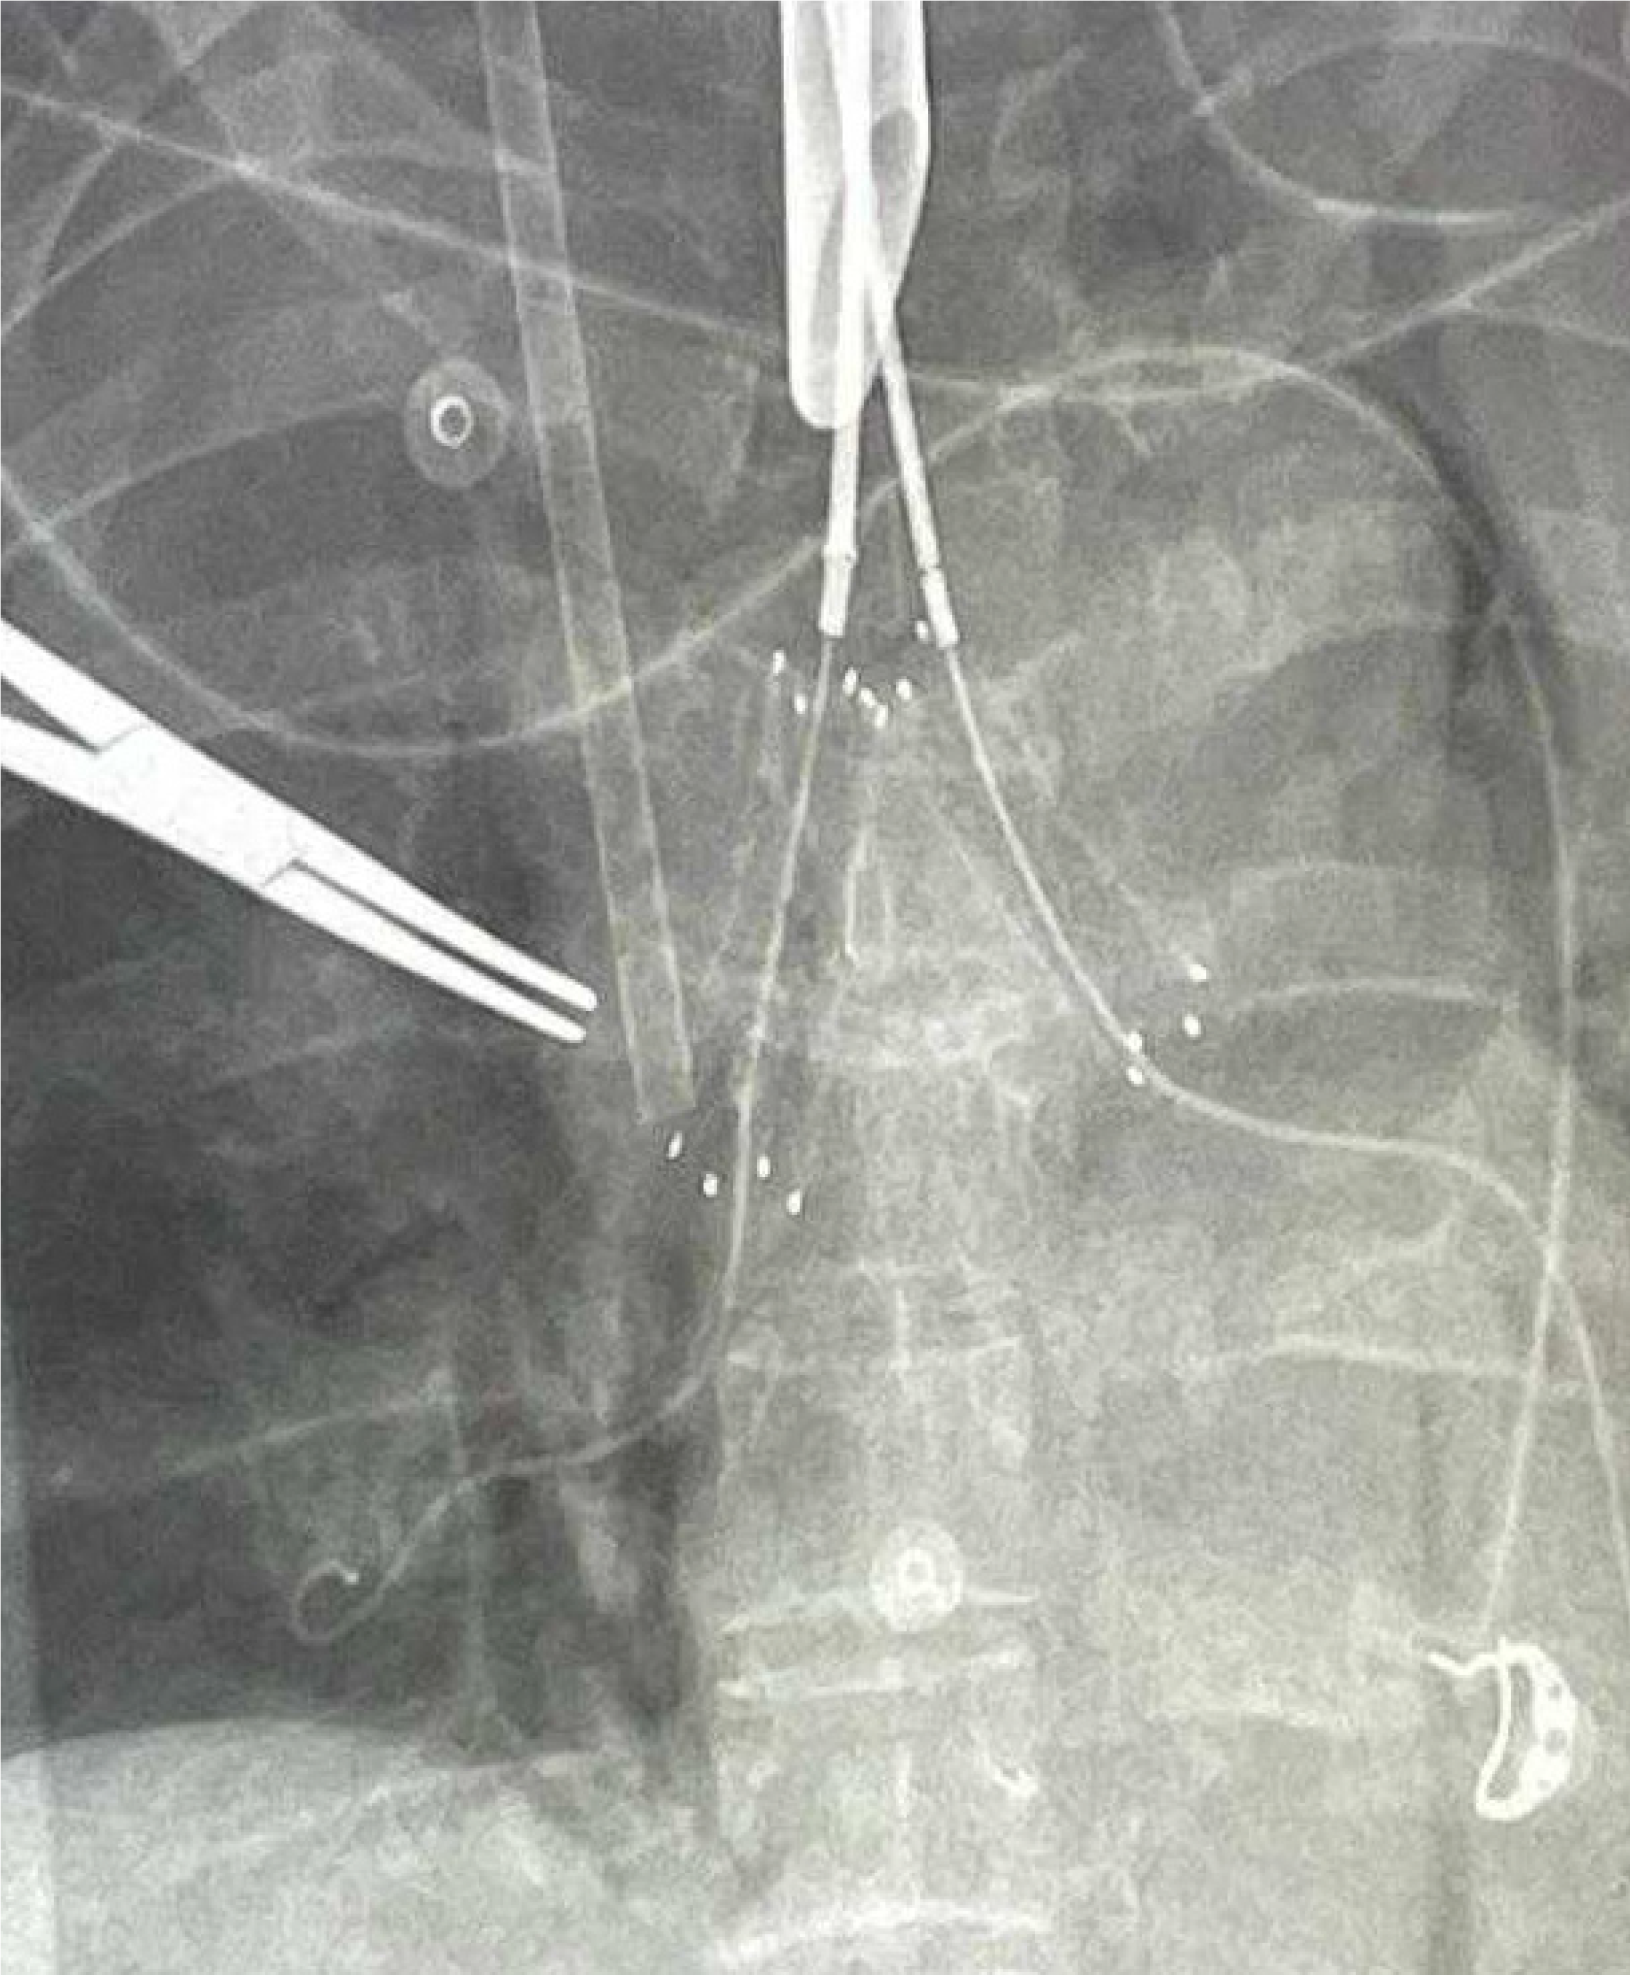

No systemic anticoagulation was administered in the perioperative period, and we did not observe any issues with circuit clotting or ECMO membrane dysfunction. Only one patient developed tension pneumothorax whilst on ECMO, which was unrelated to ECMO. This complication was unrelated to ECMO itself. The cause was tracheal perforation during intubation due to the sharp end of a Tribute endotracheal tube stylet in a patient with severe tracheal stenosis. The situation was recognized promptly and managed appropriately. We did not observe ECMO-related complications. Table 1 summarizes the patients’ data, including demographics, diagnosis, computed tomography (CT) findings, surgical and ECMO procedures, and outcomes. Figures 2, 3, 4 and 5 are examples of airway difficulties in our cohort (Fluoroscopy X-ray, CT scan, and bronchoscopy imaging). Pain and nutritional management were integral parts of patient care. Pain control was achieved using multimodal analgesia, including opioids and sedatives tailored to each patient's needs. Nutritional support was initiated early, with a preference for enteral feeding; parenteral nutrition was used when enteral access was not feasible or contraindicated.